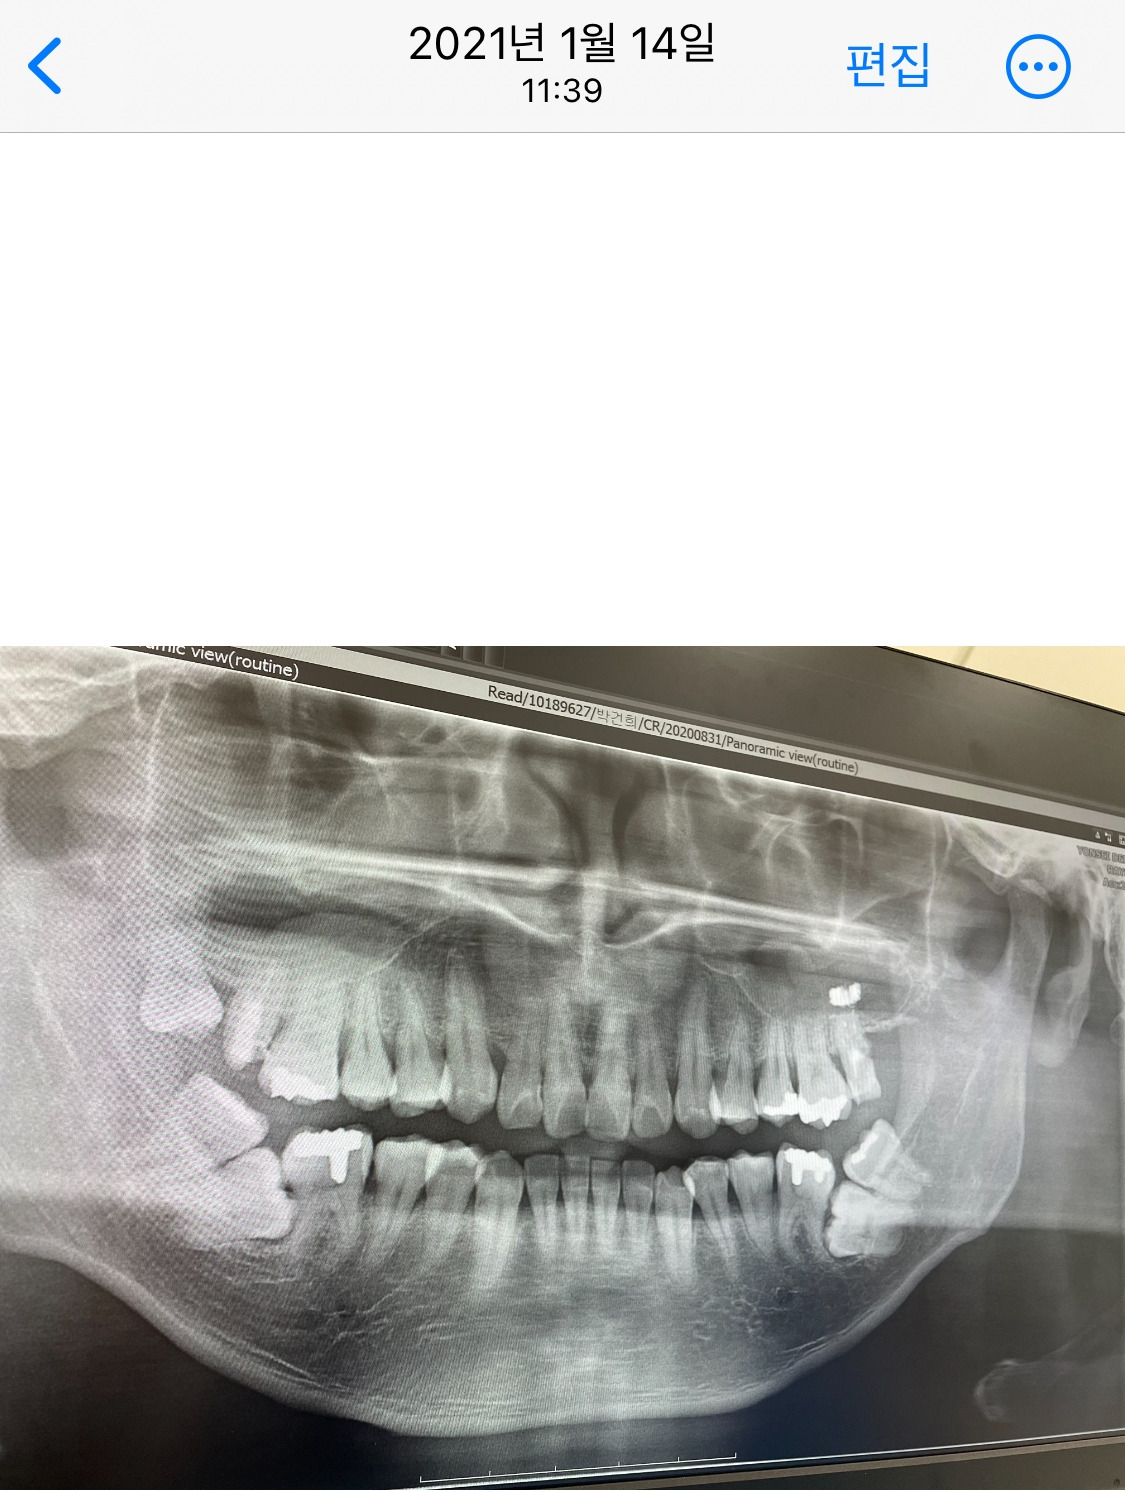

2021년 1월과 2024년 10월, 오른쪽 어금니 임플란트 결정

사랑니와 어금니 양쪽 다 매복치라는 사실을 알았을 때,

나에겐 두 가지 선택권이 있었다.

사랑니를 빼고 어금니를 교정하는 몹시 어렵지만 내 치아를 지키는 길,

그리고 둘 다 발치하고 임플란트를 하는 길.

매복치를 들어 올리자 오랜 시간 매복된 탓에 치아는 망가져 있었고, 치료가 시급했다.